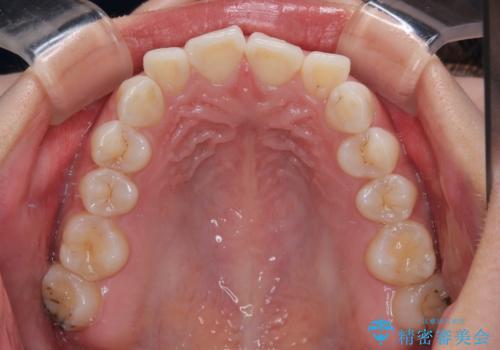

- 前歯のデコボコと突出感を気にして来院された患者様です。

極力目立たない装置を希望とのことで、インビザラインを用いて非抜歯で矯正治療を行うこととしました。

事前に親知らず2本を抜歯し、多少歯列を後方に移動できるように準備をした上で、なるべく歯と歯の間を削ることなくデコボコを解消できるように計画しました。

前歯の捻れを改善するとともに、口元が少しでも引っ込むように治療計画を立て、仕上げることができました。